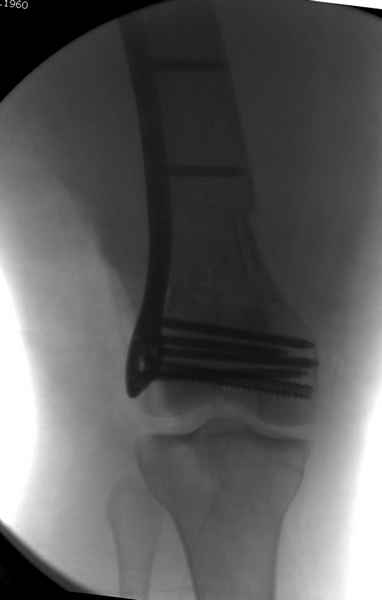

Уважаемые коллеги! От имени Алексея Смирнова всем спасибо за обсуждение. Больной прооперирован. Снимки в приложении.

При наличии различных имплантов, любые варианты: слева (полу) открытым - мининвазивным, а справа закрытым интрамедуллярным методом, его считаем более чем приемлемым для фиксации данных переломов.

Проксимальная и дистальная блокировка, независимо от техники введения штифта, ретроградно или антеградно, гарантирует сращение сегментарных переломов бедра без укорочения. Штифты диаметром 12 мм с блокировкой сверху и вниз двумя шурупами выдерживают вес 75 кг больного, что позволяет раннюю профилактику контрактур.

Из-за вариабельности установки дистальных шурупов и возможности перкутанного введения проксимально предпочитаем DePuy Polyax, хотя на сегодняшнем маркете множеств вариантов фиксации дистального бедра перкутанном методом.